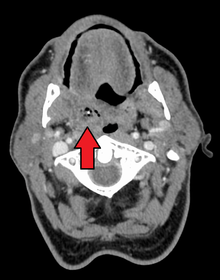

| Right sided peritonsillar abscess | |

Physical signs of a peritonsillar abscess include redness and swelling in the tonsillar area of the affected side and swelling of the jugulodigastric lymph nodes. The uvula may be displaced towards the unaffected side.